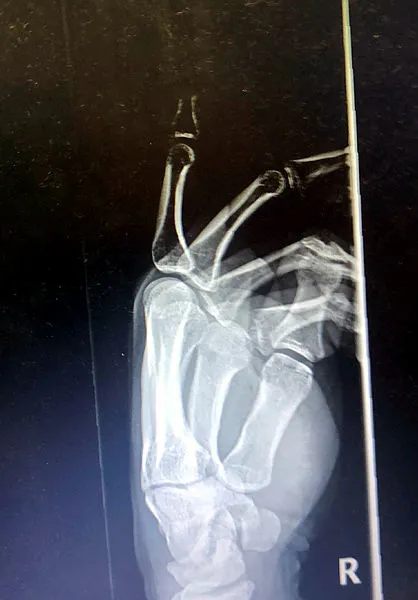

Makine mühendisi Berk Altınelli'nin, geçtiğimiz Şubat'ta yurt dışında açık denizde görevdeyken, kaza sonucu sağ el işaret parmağı orta ekleminden koptu. Helikopterle acilen Malta'da bir hastaneye götürüldü ama doktorlar parmağının dikilmeyeceğini, çöpe atmasını söyledi. Altınelli, pandeminin zor koşullarına rağmen 19 saati bulan film gibi bir operasyonla Türkiye'ye getirildi ve kopan parmağı 11 saat süren bir ameliyatla yerine dikildi.

Parmağından vazgeçmeyen genç mühendis İstanbul'da yaşayan diş hekimi dayısını aradı, bu ameliyatı Türkiye'de yapılıp yapılamayacağını sordu. Annesi Alev Altınelli ile birlikte dayısının da uğraşları sonucu aile rekonstrüktif cerrahi mikrocerrahi alanında çok başarılı ameliyatlar gerçekleştiren Prof. Dr. Mehmet Veli Karaaltın'a ulaştı. Prof. Dr. Karaaltın, normalde uzuv kopmalarında maksimum 8-9 saat içinde uzvun yerine dikilmesi gerektiğini söyleyerek "Risk alıyoruz ama deneyeceğim" dedi. Berk Altınelli'nin neredeyse 24 saati bulan film gibi Malta-Türkiye parmak kurtarma operasyonu bu cümleyle başladı ve literatüre girecek bir ameliyatla genç mühendisin parmağı kurtarıldı.

Literatüre girecek operasyonu gerçekleştiren Estetik, Plastik ve Rekonstrüktif Cerrahi Uzmanı Prof. Dr. Mehmet Veli Karaaltın ise "Süreyi duyar duymaz ilk dediğim şey, olası 8-10 saatlik sınırı epey aştığını, hatta tur döndüğünü, 24 saate kadar uzayabileceğini öğrenince, hastanın yakını olan meslektaşıma 'Deneyeceğiz, başarmaya çalışacağız' dedim sadece. Bazı şeylerin telafisi yok, bir mühendisin işgücü kaybına uğraması çok ciddi bir kayıp. Hem ülke için, hem kendisi için, hem de ailesi için. Bir mühendisin yetişmesi yıllar alıyor. Kitabi bilgiye göre bu kadar süre geçtikten sonra bu ameliyatta başarılı olma ihtimaliniz neredeyse yok. Ben aslında bir risk aldım. Çünkü başarısız olursam, aile anlayışlı baksa da, cerrahi bir başarısızlık olacaktı benim için. Ama hastanın yaşı, konumu yaşayacağı kaybın risklerini düşününce denemeye karar verdim" dedi.

Berk Altınelli'nin çok şanssız bir dönemde böyle bir kaza geçirdiğinin altını çizen Prof. Dr. Karaaltın, "Pandemi var, tarifeli uçuşlar neredeyse yok. Buraya getirilmesi bir hayli zor oldu. Ertesi günü buldu. Tabii ki normal koşullarda ambulans uçak da olabilirdi ama bu şartlar maalesef ona elverişli değildi. 17'nci saatte buraya ulaşabildim" diye konuştu. Uzuv kayıplarında doku ölümünün kansız kalma yani iskemi nedeniyle gerçekleştiğine işaret eden Prof. Dr. Karaaltın, "Parmak, bu açıdan biraz daha dayanıklı bir uzuv. İçinde kas dokusu neredeyse yok. Daha çok bağ dokuları, cilt ve kemik doku var. o açıdan şanslıydık sadece. Bizim yaptığımız ameliyat ise literatüre girecek nitelikte bir operasyon oldu. Çünkü çok uzun bir süre sonra yapılabildi. Berk ameliyattan çıkınca ağladı ve bana sarıldı parmağını kurtarabildiğimiz için. Bu da parmağını kaybetse onda nasıl bir etki oluşacağını (yani aldığımız riske değdiğini) bir kere daha gösterdi" şeklinde konuştu.

"PARMAĞIN KANLANMASI 25'İNCİ SAATTE OLDU"

Yaralanmalarda bazen uzuv kısaltarak organı kurtarmak gerektiğini söyleyen Prof. Dr. Karaaltın, sözlerini şöyle sonlandırdı: "Çünkü azıcık kısa ama işleyen bir parmak olur. Biz o stratejiyi uyguladık. Ama en büyük problem, ezilme ile birlikte kopma yaralanmasıydı. Yurtdışındaki hastanede de parmak replantasyon endikasyonu olmaz demişler. Aslında kitabi olarak doğru. Ama hastanın koşullarına göre bazen risk almak gerekebiliyor. Parmağın kanlanma saati 25 saati buldu. Ben damarı onarıp klempi açıp parmağa kan gideceği zaman duraksadım ve büyük bir heyecanla bekledim. Bakalım parmak, ameliyatımıza cevap verecek mi diye. Klempi açtıktan sonra parmak kanlanınca da çok mutlu oldum. Ameliyatlardan önce saatimi genellikle çıkarır ve masanın üzerine koyarım. Zamanı unuturum. Mikrocerrahi böyle bir şey. Çok heyecanla girdiğim ameliyatlar bunlar. Çünkü uzuv kurtarıyorsunuz. Açıkçası saate bakmadım ama sanırım 11 saati bulmuş. Türkiye, mikrocerrahi açısından bence Avrupa'da en iyi konumda. Şimdiki genç meslektaşlarımız pek istemiyorlar mikrocerrahiyi. Çünkü çok zahmetli ve yorucu. Ama benim onlardan ricam, lütfen bazıları da bu alana girsin. Çünkü ülkenin buna ihtiyacı var"